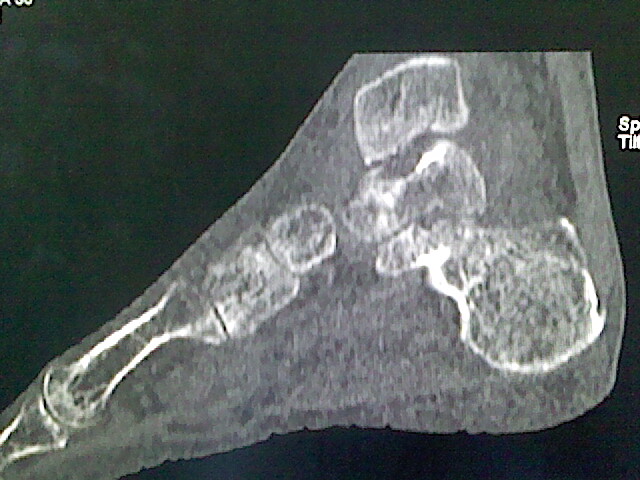

男,76岁,左小腿疼痛,不能站立

本例骨质改变主要表现为滑膜或韧带区的骨侵蚀融解(胫腓联合区骨质破坏无硬化边),距骨后部骨质破坏区有硬化边及死骨样改变.所以,本例考虑关节结核可能性大,绒毛膜结节性滑膜炎多发于中年,且极少见于膝髋以外的关节,骨质硬坏也以压陷吸收为主,有明显的硬化边,骨膜增生呈结节状(可以mr鉴别),所以本例暂除外.

另不除外可引起相似表现的其他炎症如布氏杆菌性关节炎等